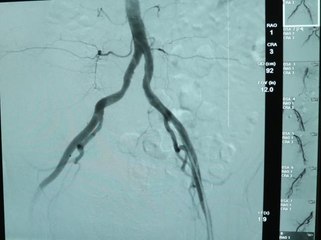

İstanbul 1 Bypass,18 Anjiyo, 6 Stent, 4 Balon Anjiyografisi Yapıldı; Doğum Gününde Sağlığına Kavuştu